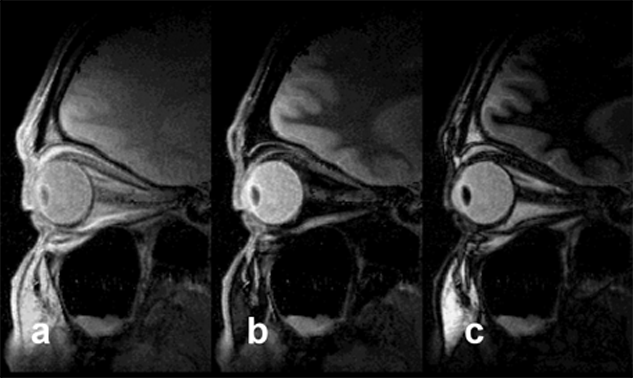

Figura 10-10:

STIR. In all images, TR = 4000 ms, TE = 10 ms; (a) TI = 50 ms, (b) TI = 240 ms, (c) TI = 450 ms. The fat­ty tissue close to the optic nerve disappears with a TI of ap­pro­xi­ma­te­ly 240 ms. Signal suppression is based on T1 relaxation times and not tissue specific. STIR should be used before in­ject­ing con­trast agents.